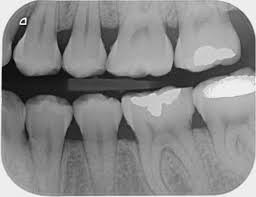

Radiografías periapicales e interproximales

Imágenes más detalladas y localizadas que permiten ver las raíces de los dientes, detectar caries ocultas o evaluar infecciones.